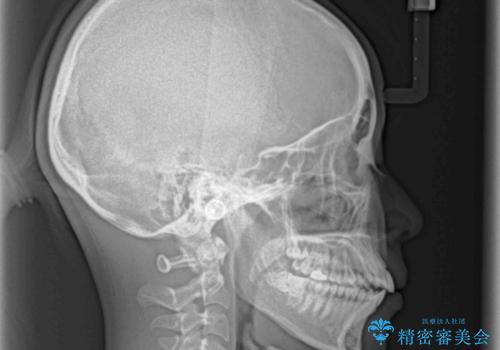

- 口元の突出感を気にして来院された患者様です。

口元を積極的に引っ込めるために、上下左右の第一小臼歯を4本抜歯することとし、ワイヤー装置による矯正治療を行うこととしました。

上下前歯がくちばしのように突出していましたが、抜歯矯正により口元が引っ込み、唇が閉じやすくなり、鼻の下の膨れた感じも解消されました。